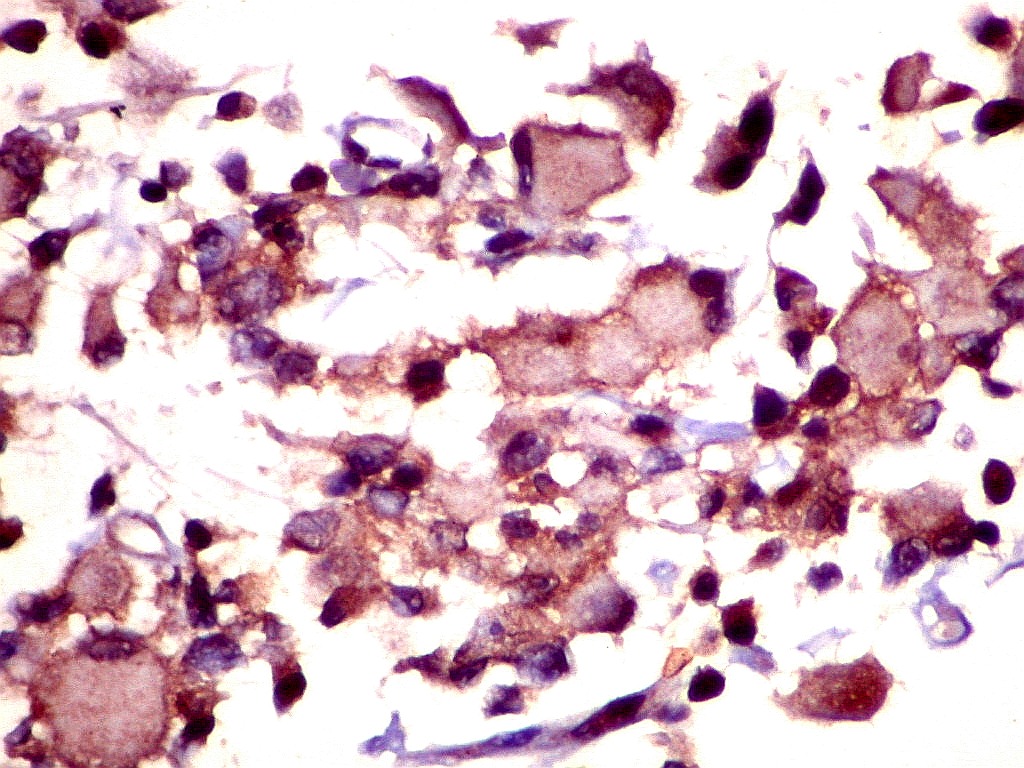

HHF-35. Actina muscular específica é expressada no citoplasma das células rabdóides neoplásicas, indicando diferenciação muscular. Para mais sobre este anticorpo, clique.

1A4.    Actina alfa de músculo liso (smooth muscle actin), reconhecida pelo anticorpo 1A4.  Ausente nas células neoplásicas, presente nos vasos do tumor. Para mais sobre este anticorpo, clique.